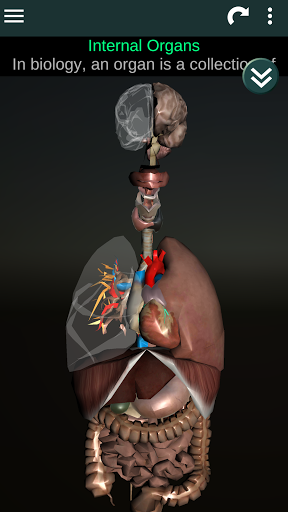

Показує 3D анатомічну модель основні органи людського тіла та опис кожного з них.

Що в додатку?

* Легкий доступ і навігація (масштабування, 3D-обертання).

* Описи кожного органу.

Ця програма розроблена, щоб доповнити вивчення анатомії в різних освітніх, медичних і культурних умовах.